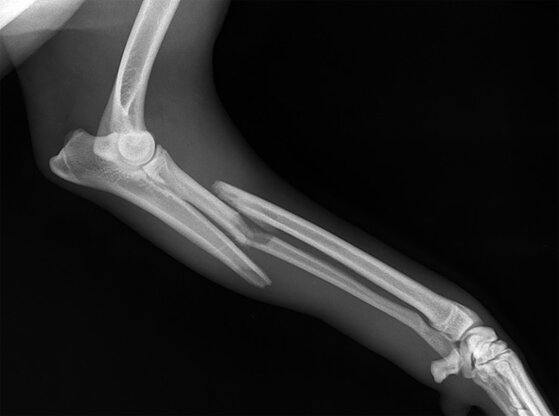

ПЕРЕЛОМЫ ПЛЕЧА И ПРЕДПЛЕЧЬЯ

Переломы плеча и предплечья могут быть открытыми и закрытыми, со смещением и без смещения отломков и т.д. Переломы без смещения очень трудно отличить от ушибов, поэтому помощь и в том и другом случае оказывают как при переломах.

Первая помощь при переломах плеча и предплечья

• Положить между грудью и рукой свернутую в несколько слоев косыночную повязку или любую другую ткань и помочь пострадавшему поддерживать руку, не опуская предплечье.

• Сделать поддерживающую повязку и привязать руку к туловищу другой косыночной повязкой.

• Вызвать скорую помощь или доставить пострадавшего в лечебное заведение.